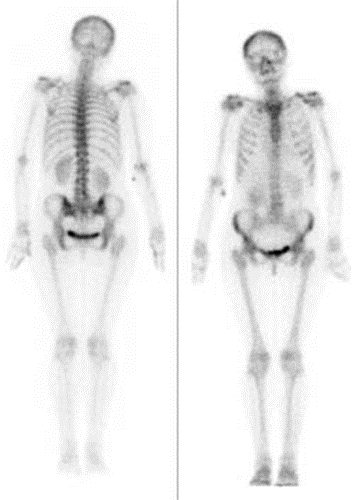

Którą metodą zostało wykonane badanie kręgosłupa zobrazowane na zdjęciu?

Ilustracja do pytania 13

A. Radiologii klasycznej.

B. Tomografii komputerowej.

C. Rezonansu magnetycznego.

D. Scyntygrafii statycznej.